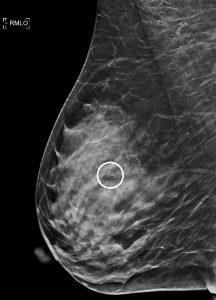

Master the accreditation process and case review of stereotactic breast biopsies with this detailed CME course. This training offers an in-depth understanding of the ACR's accreditation requirements, personnel qualifications, and quality control protocols for stereotactic biopsy facilities. Learn essential techniques for patient selection, equipment handling, and troubleshooting common pitfalls, including positioning challenges and anesthesia management. Real-world case reviews help refine your understanding of biopsy procedures for calcifications, masses, and architectural distortions. This course is designed for radiologists, technologists, and medical physicists seeking to enhance their expertise in breast disease diagnosis and accreditation.